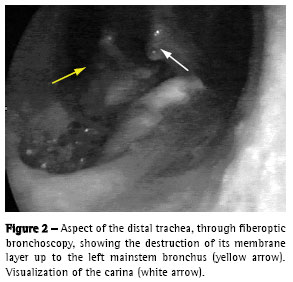

The control chest X ray, after upper digestive endoscopy, revealed left pneumothorax. Left thoracic drainage was performed with immediate lung re-expansion. In the fiberoptic bronchoscopy, we observed an area of destruction of the distal trachea, carina and left bronchus of approximately 3 x 1.5 cm (Figures 2 and 3), as well as exposure of the mediastinal tissue, together with de-epithelization and retraction of the epiglottis and right vocal chord.